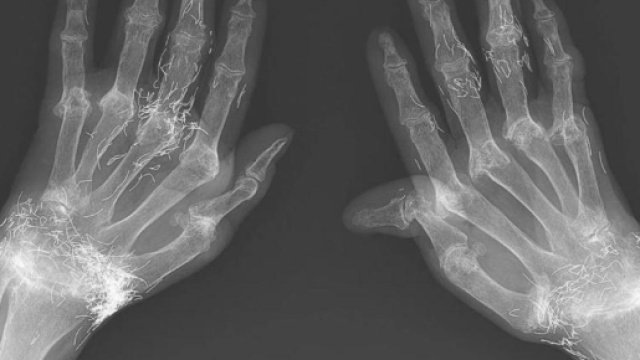

Non riusciva più a sopportare quel forte dolore alle mani e si era recata in Ospedale. I medici, dopo aver sottoposto gli arti a una lastra hanno fatto una scoperta sconcertante. La protagonista di questo curioso episodio è una 58enne coreana che non riusciva più a muovere le mani per il forte dolore. Un male indescrivibile che l'aveva portata a recarsi in ospedale per farsi curare. Il personale sanitario, per accertare l'origine del suo male, le aveva fatto una lastra. Il referto è stato incredibile: in quelle mani c'era oro. Perché la signora aveva il metallo nobile nella carne delle sue mani?

I medici dell'ospedale coreano, dopo aver fatto alla 58enne una serie di domande, hanno scoperto che la paziente si era sottoposta per anni a sedute di agopuntura. Nelle dita e nei polsi della coreana erano rimasti residui di filamenti d'oro degli aghi che venivano usati durante le sedute di agopuntura. Svelato l'arcano, dunque. La signora aveva optato per l'agopuntura per ridurre il forte dolore alle mani. Invece di diminuire, però, quel patimento aumentava.

La donna coreana aveva 18 anni quando iniziò ad accusare forti dolori alle mani. A 48 anni le venne diagnosticata l'artrite reumatoide, una patologia che, nel corso degli anni, aveva provocato la deformazione delle sue mani.

Il personale sanitario dell'ospedale coreano pensa che il forte dolore alle mani non sia dovuto all'oro ma all'artrite reumatoide, patologia per cui attualmente non esiste terapia. Se la signora si fosse sottoposta a cure a base di farmaci, dopo la diagnosi, probabilmente le sue sofferenze sarebbero state minori.